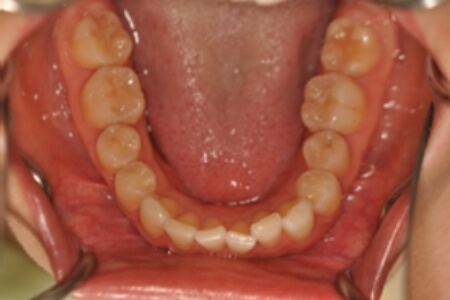

でっ歯(非抜歯)【2104】

治療内容の詳細 初診時30歳の女性で、全体的ながたつきを主訴として来院されました。

検査の結果、過蓋咬合を伴う、アングルⅡ級1類不正咬合と診断しました。

治療としては、非抜歯の上、セルフライゲーションブラケット装置(デーモンシステム)とマウスピース矯正装置(インビザライン)で歯の配列を行いました。

同時に顎間ゴムにて咬合関係の改善を行いました。